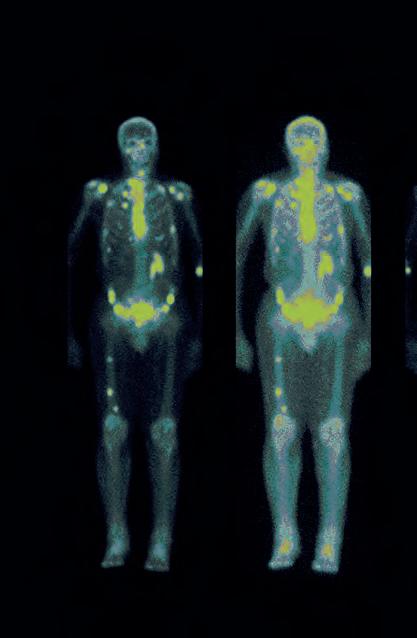

We ask seven experts what the future holds for artificial intelligence (AI) in relation to medical physics and clinical engineering. Questions range from the new standard framework BS 30440, to regulation and AI’s impact on our current and future workforce needs.

Junior staff, more likely to be keen adopters, may require support to improve their skills in communicating and influencing senior stakeholders to drive digital transformation...

– Richard Meades, Radionuclide Therapy Lead Physicist page 14

RICHARD

While the first AI-driven tools are starting to appear in a wide range of clinical applications, medical physicists/clinical engineers are rarely the intended primary users. In nuclear medicine at least, I am yet to see the wide availability and adoption of AI-driven tools that serve the needs of our workflows. It would be great to see this change, as AI in the form of machine learning is just a tool, freely available for anyone to use in developing solutions to their problems to improve their workflows and patient outcomes.

Currently, clinical scientific computing (CSC) teams work on, for example, data curation and product monitoring, which can be effort and time intensive. In the future, AI may, in part, automate those processes, such as the curation of physiological measurements via a large language model or the quality assurance/quality control of PET/CT systems conducted by AI watchdogs as part of an AI-driven evaluation project overseen by a CSC team.